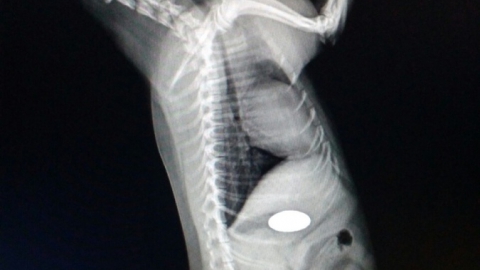

Специалисты саратовской ветлечебницы №1 спасли пса, проглотившего пуговицу. Как сообщает управление ветеринарии правительства Саратовской области, помощь потребовалась йоркширскому терьеру Жуже.

"Животное отказывалось от пищи, было вялым. Ветеринарные специалисты с помощью рентгена определили, что собака проглотила пуговицу, и она находится в желудке", - сообщают ветеринары.

Двухсантиметровую пуговицу из терьера достали, сейчас Жужа успешно проходит восстановительный период.